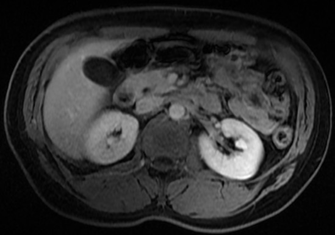

Subsequently, the patient reported a similar episode a year ago while riding a bike, which resulted in a wrist fracture. However, it was not studied by then. During his hospitalization the patient presented repeated episodes of hypoglycemia, so studies were expanded, a lipid profile, thyroid function, and plasma cortisol were performed, all of which were normal, and possible infection was ruled out. It was evaluated in conjunction with the endocrinology service, who indicated imaging studies and a 72 hours fasting test because of insulinoma suspicion. Computed tomography (CT) with abdominal contrast and magnetic resonance cholangiopancreatography (MRCP) were performed, showing a cystic image in the liver without other significant anomalies (Figures 1 and 2). A 72-hour carbohydrate fasting test was performed, which ended after 14 hours due to symptoms of hypoglycemia and fingerstick blood glucose of 36 mg/dL (2 mmol/L). Laboratory tests were taken immediately, confirming venous blood glucose of 35 mg/dL (1.94 mmol/L) and insulin of 46.7 uIU/mL (high, reference range 2.6 - 25 uIU/ml). Then dextrose intravenous was administered and the symptoms resolved. Unfortunately, in our hospital there is no availability to measure C-peptide, beta-hydroxybutyrate, proinsulin levels and anti-insulin antibodies.

Figure 1 Abdominal contrast enhanced CT indicating a morphology cystic image in the left lobe liver.